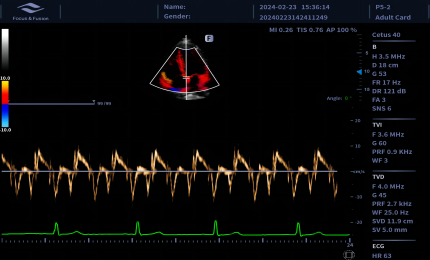

Technologia krzywoliniowego M-Mode (CAM) umożliwia wyświetlanie wszystkich przestrzennych i czasowych relacji ruchów segmentów mięśnia sercowego podczas cyklu sercowego w sektorze skanowania. Zapewnia to nową metodę pomiaru do ilościowej analizy zaburzeń ruchów segmentów mięśnia sercowego podczas fazy skurczowej lub rozkurczowej.

Obrazowanie tkankowe metodą Dopplera (TDI) to solidne i powtarzalne narzędzie echokardiograficzne, które wykorzystuje efekt Dopplera do oceny charakterystyk ściany mięśniowej w całym cyklu sercowym, obejmując prędkość, przemieszczenie, deformację oraz timing zdarzeń. Pozwala na ilościową ocenę zarówno globalnej, jak i regionalnej funkcji oraz timing zdarzeń miokardialnych.